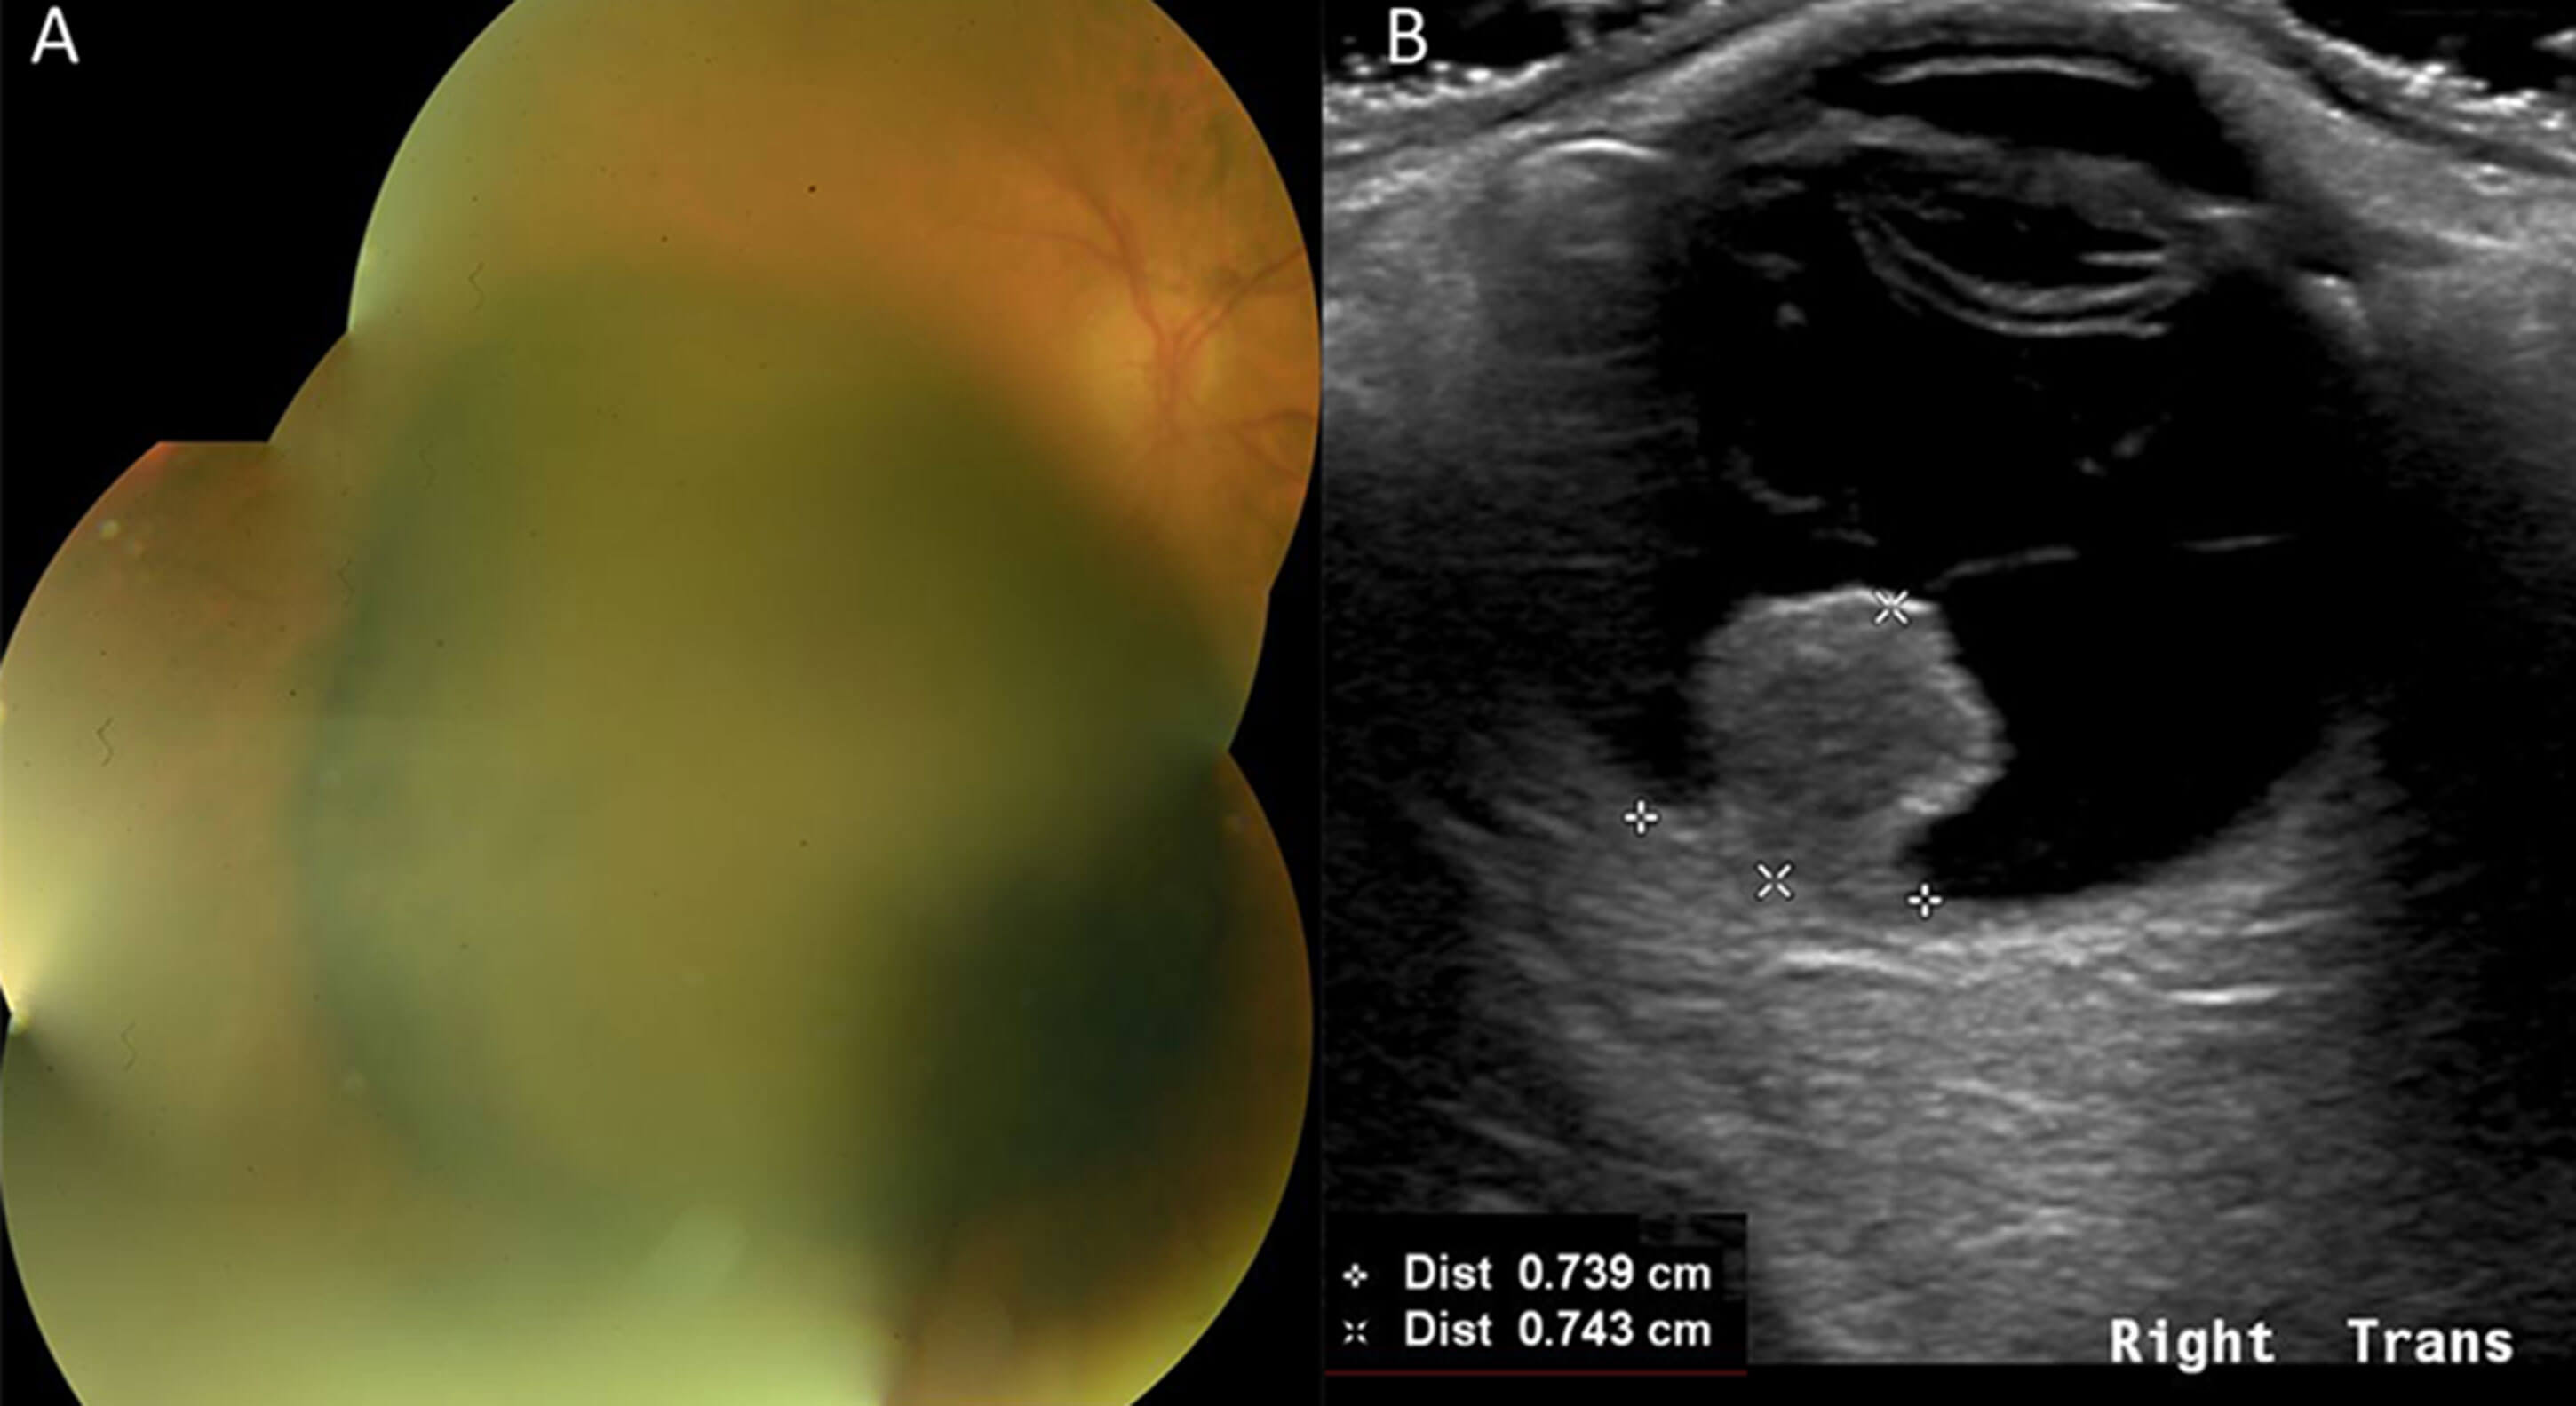

Figure 3: Right choroidal melanoma (AJCC Stage 2A); A: Large pigmented choroidal mass; B: Eye Ultrasound Scan highlights collarstud morphology,with Proton Beam Therapy (PBT) Measurements. [Basal dimensions 8.0 x 7.4mm. Maximum thickness 7.4mm]. This choroidal melanoma responded well to PBT with reduction in basal dimensions and thickness.